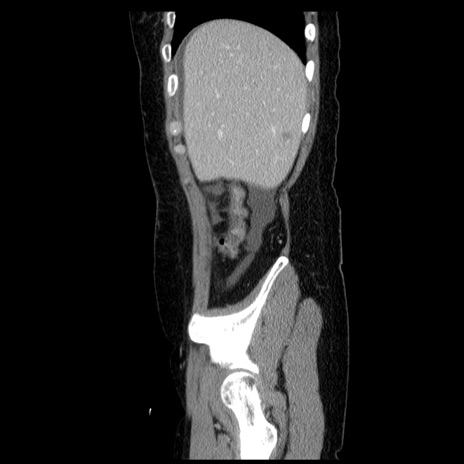

冠状断像